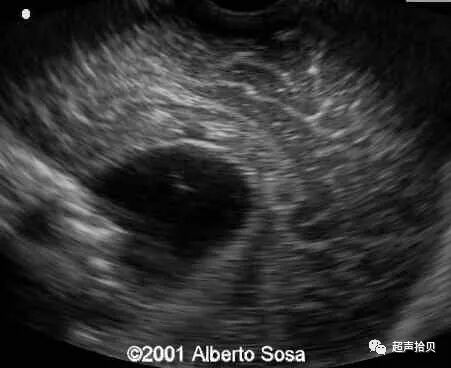

图1:横向声像图显示位于中线蛛网膜囊肿(C), 彩色多普勒没有血流显示;

图2:冠状超声图显示位于后颅窝蛛网膜囊肿